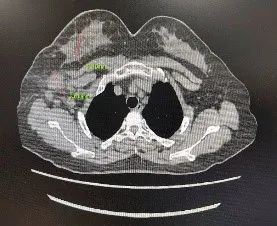

B超:右侧乳腺6点可见一大小约31×18mm低回声结节;右侧10点可见一大小约30×18mm低回声结节;BI-RADS分级:5类;右侧腋窝明显肿大淋巴结,大小约21×19mm。

图1. B超 2021.9.23